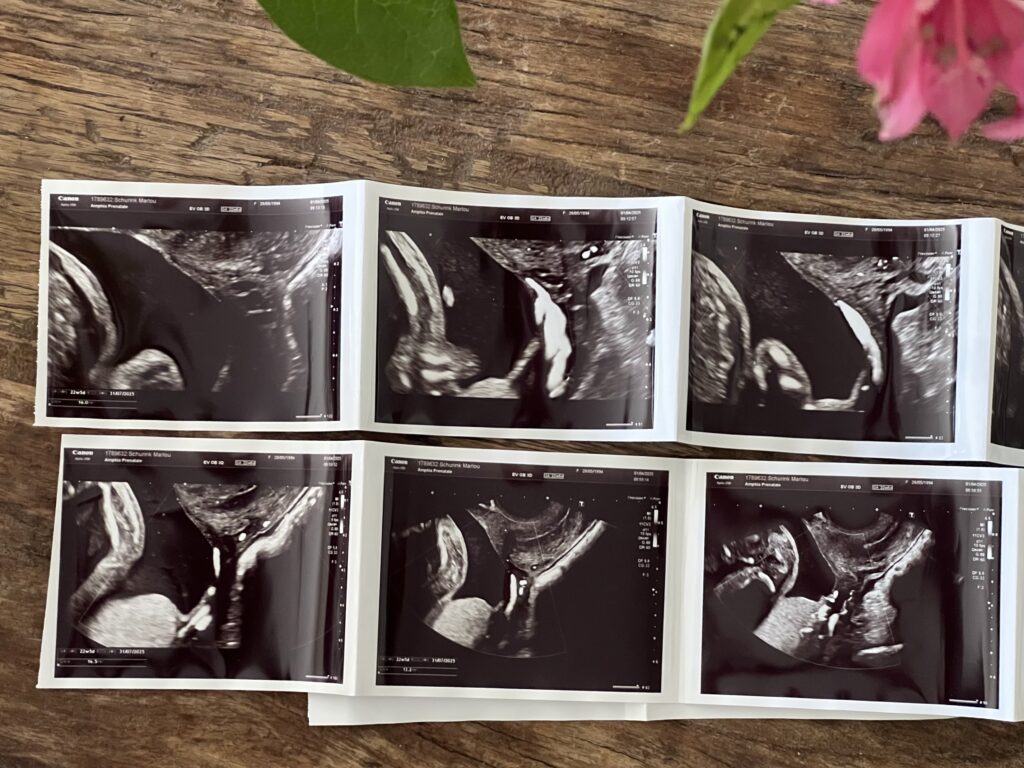

De 20-wekenecho was een moment waar ik naar uitkeek. Weer even spieken naar ons kleintje, alles laten checken en hopelijk met een gerust hart naar huis. Maar toen de echoscopist zei dat ze de nieren en het geslacht beter wilde controleren, voelde ik een lichte spanning. Uitwendig was het niet goed te zien, dus stelde ze een inwendige echo voor. Geen probleem voor mij. Ze was professioneel en checkte steeds of ik me op mijn gemak voelde. Totdat ze stilviel. “Ik denk dat ik een bloedvat zie bij de baarmoedermond,” zei ze uiteindelijk. “Met 32 weken krijg je een echo in het ziekenhuis.” Vreemd. Maar oké. Niet direct paniek.

Eerst de standaard checks: hoofdje, buikje, het hartje, alles groeide goed. Daarna ging hij door naar onder. De placenta en de bloedvaten. “Ja hier loopt inderdaad een bloedvat,” zei hij na een paar minuten. “De bloedader zit slechts 1,6 cm van de baarmoedermond af.” Een tweede arts werd erbij gehaald. “Bevestig jij dit?” vroeg hij. Ze keek en knikte. “Ja. Vasa previa.“